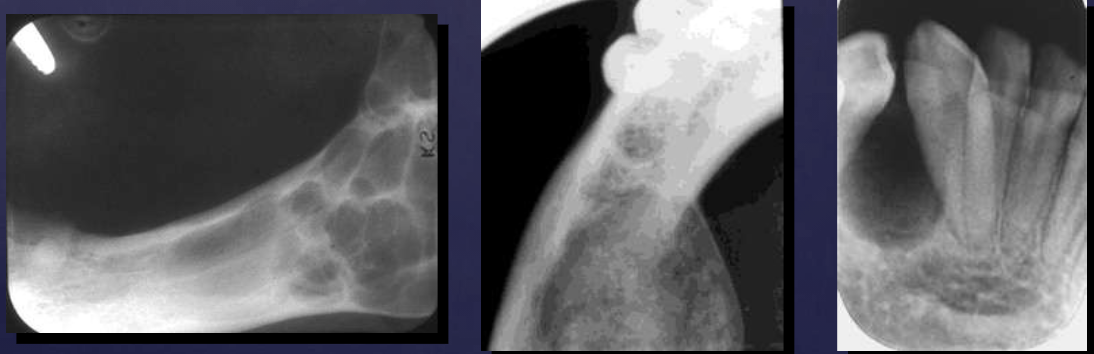

radiographic features of cementoblastomas

multiple punctate radiopacities within a well-defined radiolucency

homogeneous radiopaque mass

mass attached to 1st mandibular molar roots

obscured root outline, external resorption

radiolucent halo - continuity w/ PDL

sclerotic border

differentiate cementoblastomas vs. hypercementosis

cementoblastomas: globular

hypercementosis: bulbous, more tooth-shaped

radiographic features of compound odontomas

radiolucent band/soft tissue capsule inside the cortical border

internal content is largely radiopaque: made of tooth-like structures called denticles

maybe associated w/ unerupted tooth

radiographic features of complex odontomas

internal content is largely radiopaque- made of irregular mass of calcified tissue